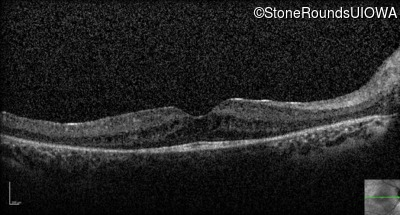

Optical Coherence Tomography - Left - 20/50

Exemplar / OCT Stack